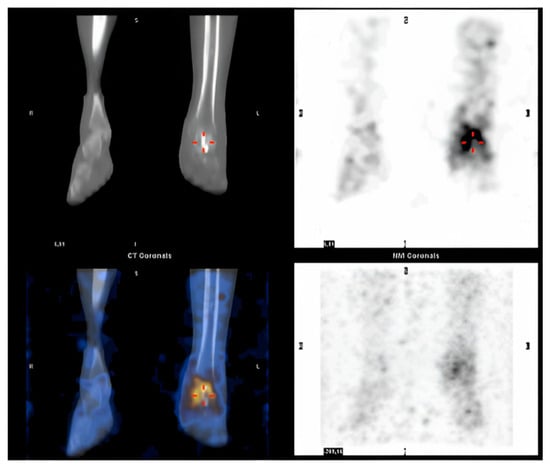

After the failure of re-implantation, two therapeutic options (arthrodesis and TTR) were presented to the patient. The patient agreed to undergo the implantation of a talar prosthesis. The prosthesis was made by 3D printing the mirrored CT scan of the contralateral talus. The customized implant was produced by casting a chromium-cobalt alloy (Sintac Srl, Trento, Italy). The talar prosthesis was manufactured using state-of-the-art laser technology by powder melting a cobalt-chromium alloy (nickel, beryllium, and cadmium free, according to standard DIN-EN-ISO 22674:2006) and included porous articular surfaces and a talar-navicular component with two channels to host the lag screws for subtalar fixation. The implant weight was 390 g. In May 2014, after complete healing of the soft tissues, the customized talar prosthesis was implanted: After an anterior-medial approach, the spacer in antibiotic-coated cement was exposed and removed. A thorough soft tissue debridement was performed, and the articular cartilage was removed from the subtalar calcaneal surface. Subsequently, the tailor-made talar prosthesis was implanted and fixed to the calcaneus by two screws (Figure 4).

Figure 4.

Total talar replacement with subtalar fixation, post-operatory anteroposterior (A) and latero-lateral (B) X-ray.